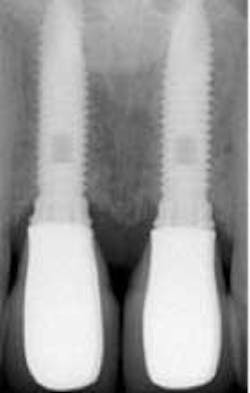

How about the concept of evidence based decisions, which we are asked to make these days? We need to be creative with our own clinical expertise, the patient’s wishes, and the available tools and products in the marketplace. This is called best practice! Dental implants are “mimic” teeth. For some time, we have known that we need to probe implants like normal teeth, and there is really no more controversy on this topic. We must establish a baseline with probing depths and radiographs.